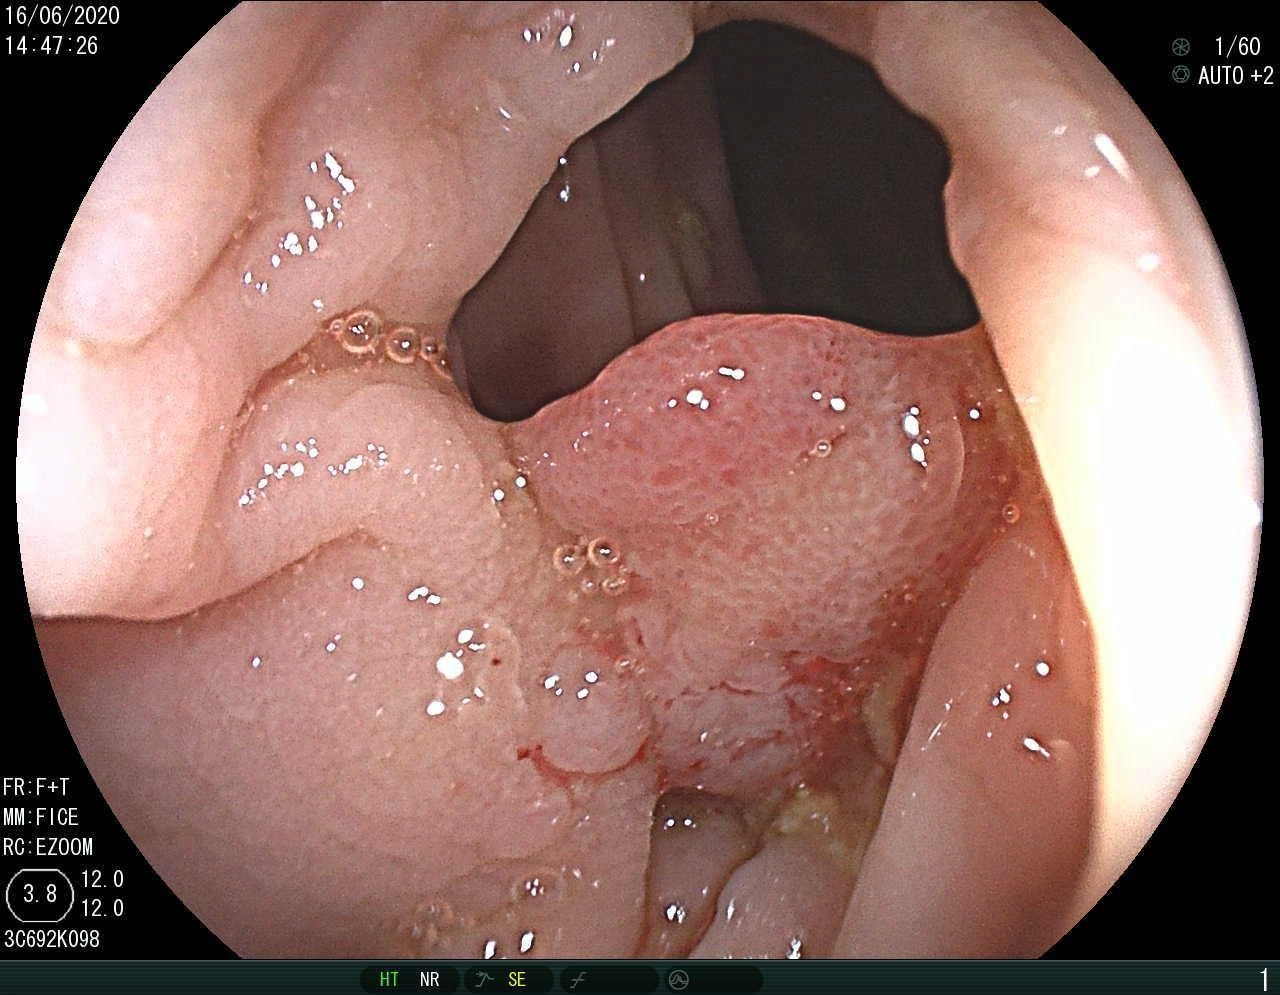

IV-A3 BKAI-IGH NeoPolyp Dataset

The BKAI-IGH NeoPolyp [26] dataset was released by the BKAI Research Center at Hanoi University of Science and Technology in collaboration with the Institute of Gastroenterology and Hepatology (IGH) in Vietnam. This dataset comprises 1,200 images, with a division of 1,000 images for training and 200 images for testing purposes. Within the dataset, polyps are categorized into neoplastic or non-neoplastic classes, represented in red and green, respectively. While an official split of 1,000 training and 200 testing samples exists, the official test ground truth is not public due to the ongoing challenge. Thus, we partition the training set into five folds to evaluate the model’s performance comprehensively. Two experiments were conducted using this dataset: binary segmentation and multi-class segmentation.

IV-C3 Results on BKAI-IGH NeoPolyp

![]() |

| (a) Inputs | (b) Ground Truth | (c) Ours | (d) EGE-UNet |

| (d) Swin-Unet | (e) MET-Net | (f) VM-UNetV2 | (g) UNet++ |

| Method | Binary | Multi-class | ||||

|---|---|---|---|---|---|---|

| MAE | Dice | IoU | MAE | Dice | IoU | |

| U-Net (2015) [1] | 0.99 | 87.25 | 81.33 | 0.92 | 67.74 | 64.11 |

| UNet++ (2020) [2] | 0.92 | 88.44 | 82.89 | 0.86 | 68.51 | 64.82 |

| EGE-UNet (2023) [28] | 3.20 | 59.98 | 49.28 | - | - | - |

| MISSFormer (2023) [8] | 0.95 | 87.98 | 81.89 | 0.87 | 70.00 | 66.40 |

| Swin-Unet (2023) [5] | 0.73 | 90.80 | 85.24 | 0.66 | 79.80 | 76.48 |

| MALUNet (2023) [29] | 1.84 | 82.09 | 69.67 | - | - | - |

| TransUNet (2024) [6] | 0.69 | 91.37 | 86.25 | 0.70 | 77.62 | 74.89 |

| MET-Net (2024) [30] | 0.74 | 91.05 | 85.99 | 0.71 | 75.96 | 73.07 |

| FSCA-Net (2024) [32] | 0.89 | 89.45 | 83.99 | 0.81 | 73.65 | 70.41 |

| VM-UNetV2 (2024) [33] | 1.26 | 87.71 | 78.16 | - | - | - |

| QTSeg (Ours) | 0.60 | 93.13 | 88.94 | 0.59 | 79.88 | 77.54 |

The experimental results of our QTSeg model on the BKAI-IGH Neopolyp dataset are presented in Table IV. The table clearly demonstrates that our QTSeg model achieves the highest scores across all metrics and tasks (binary and multi-class). Notably, QTSeg obtains the MAE, Acc, Dice, and IoU of 0.60, 99.40%, 93.13%, and 88.94%, and 0.59, 99.41%, 79.88%, and 77.54%, for the binary and multi-class tasks, respectively. Although EGE-UNet and MALUNet are characterized by their smaller parameter sizes, they struggle to converge on the poly-segmentation dataset due to inherent design limitations and model parameter constraints. In contrast, our QTSeg model demonstrates superior performance while maintaining competitive parameter values and lower FLOPs than the alternative methods. Regarding binary task, our QTSeg model achieves notable improvements of 1.76-33.15% in Dice and 2.69-39.66% in IoU. In terms of multi-class tasks, our QTSeg model gains notable improvements of 0.08-12.14% in Dice and 1.05-13.42% in IoU. The comparison in Fig. 7 showcases our model’s predictions alongside those of other methods. It is evident that our approach achieves more precise segmentation of the poly object with minimal error compared to the other methods.